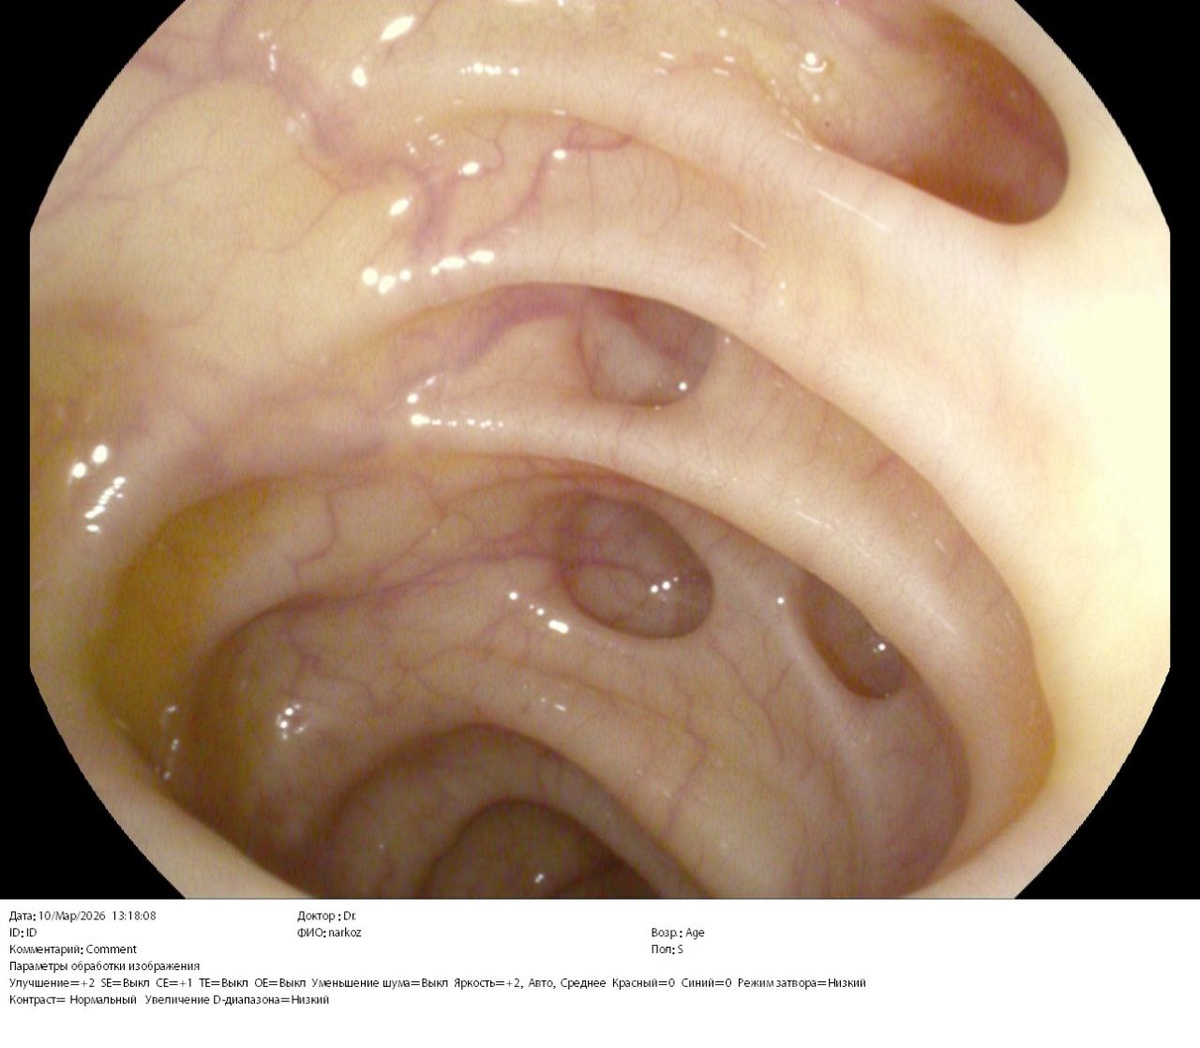

⚕️На фото множественные дивертикулы левой половины толстой кишки без признаков воспаления у пациентки 54 лет. Жалоб не предъявляет. «Случайная находка» при скрининговой колоноскопии.

✔️Итак, дивертикул - это грыжевидное выпячивание стенки полого органа.

Большинство дивертикулов толстой кишки (у 80% людей) остаются бессимптомными на протяжении всей жизни (дивертикулез), и диагноз часто ставится случайно во время колоноскопии, проводимой по другим причинам, например, для скрининга колоректального рака.

В отличие от этого, примерно у 20% развивается дивертикулярная болезнь, которая включает в себя множество клинических сценариев:

-✅️начиная от симптоматической неосложненной дивертикулярной болезни, характеризующейся рецидивирующими болями в животе, часто связанными с изменениями в работе кишечника и/или вздутием,

-✅️до острого начала симптомов и признаков (например, острая и сильная боль в животе, лихорадка и лейкоцитоз), характеризующих острый дивертикулит.

✔️Возникновение дивертикулов в стенке ободочной кишки, в первую очередь, обусловлено изменением механических свойств соединительной ткани подслизистого слоя. При этом действие внутрипросветного давления приводит к пролапсу слизистой оболочки через «слабые» участки кишечной стенки - места проникновения в нее кровеносных сосудов.